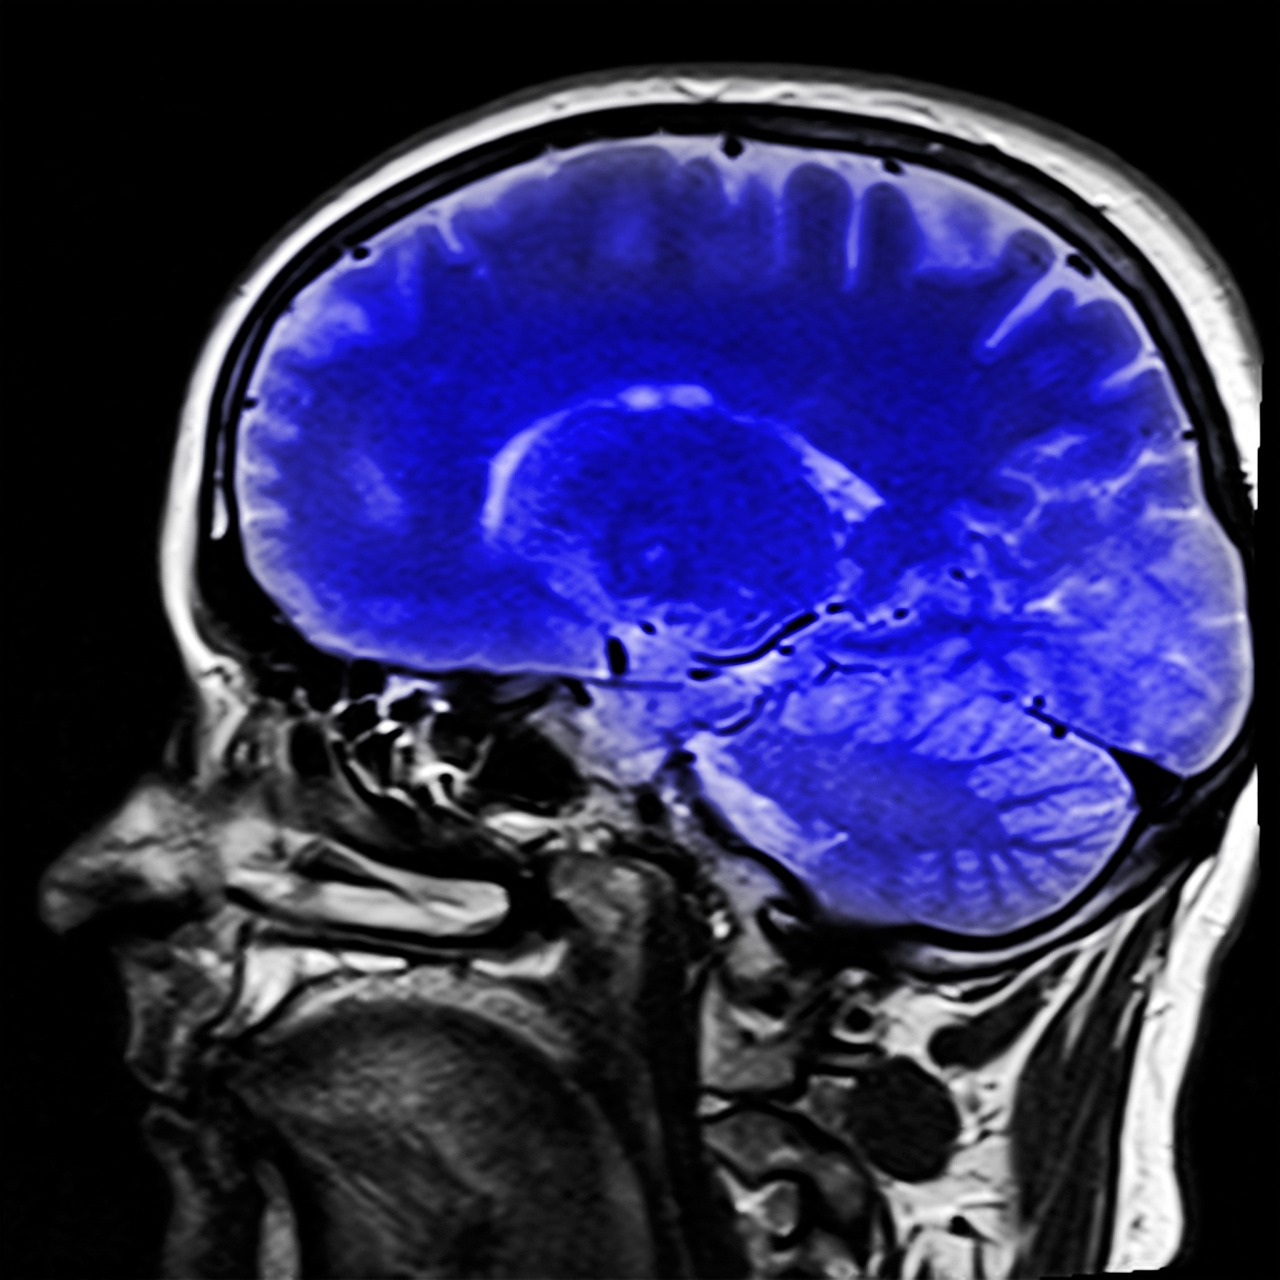

뇌수막염은 뇌와 척수를 덮고 있는 수막이라고 불리는 보호막에 염증이 생긴 것입니다. 이 질환은 박테리아, 바이러스, 곰팡이 및 기타 미생물을 포함한 다양한 감염원에 의해 발생할 수 있습니다. 다음은 뇌수막염과 관련된 일반적인 증상입니다.

뇌수막염은 뇌와 척수를 덮고 있는 뇌수막이라고 알려진 보호막에 염증이 생기는 것입니다. 그것은 박테리아, 바이러스, 곰팡이 및 기타 미생물을 포함한 다양한 감염원에 의해 발생할 수 있습니다. 뇌수막염의 주요 원인은 다음과 같습니다.